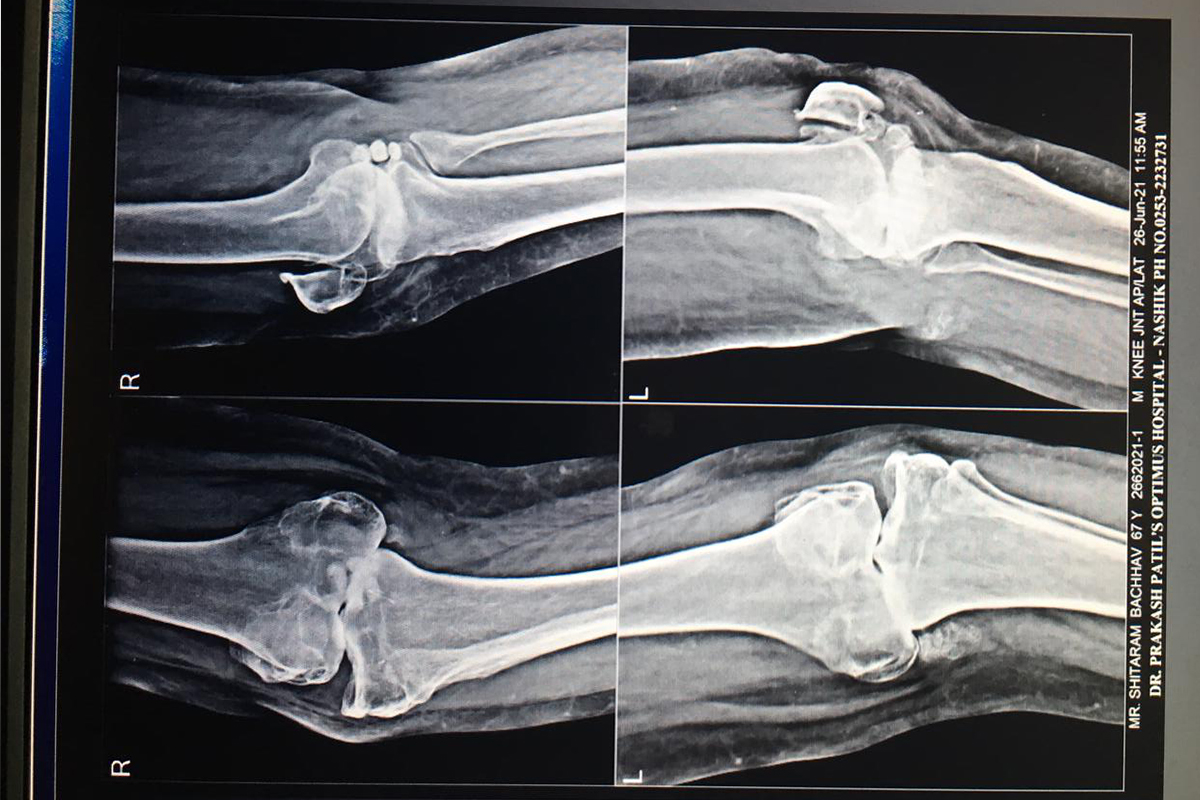

Joint Replacement